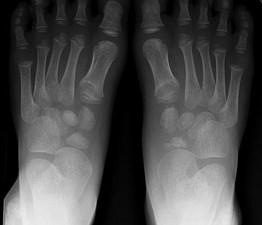

问题 男,5岁,足背肿痛,请结合图像,选出最可能的诊断 ( )

选项 A、软骨发育不全 B、剥脱性骨软骨炎 C、跗舟骨骨折 D、成骨不全 E、跗舟骨缺血坏死

答案 E